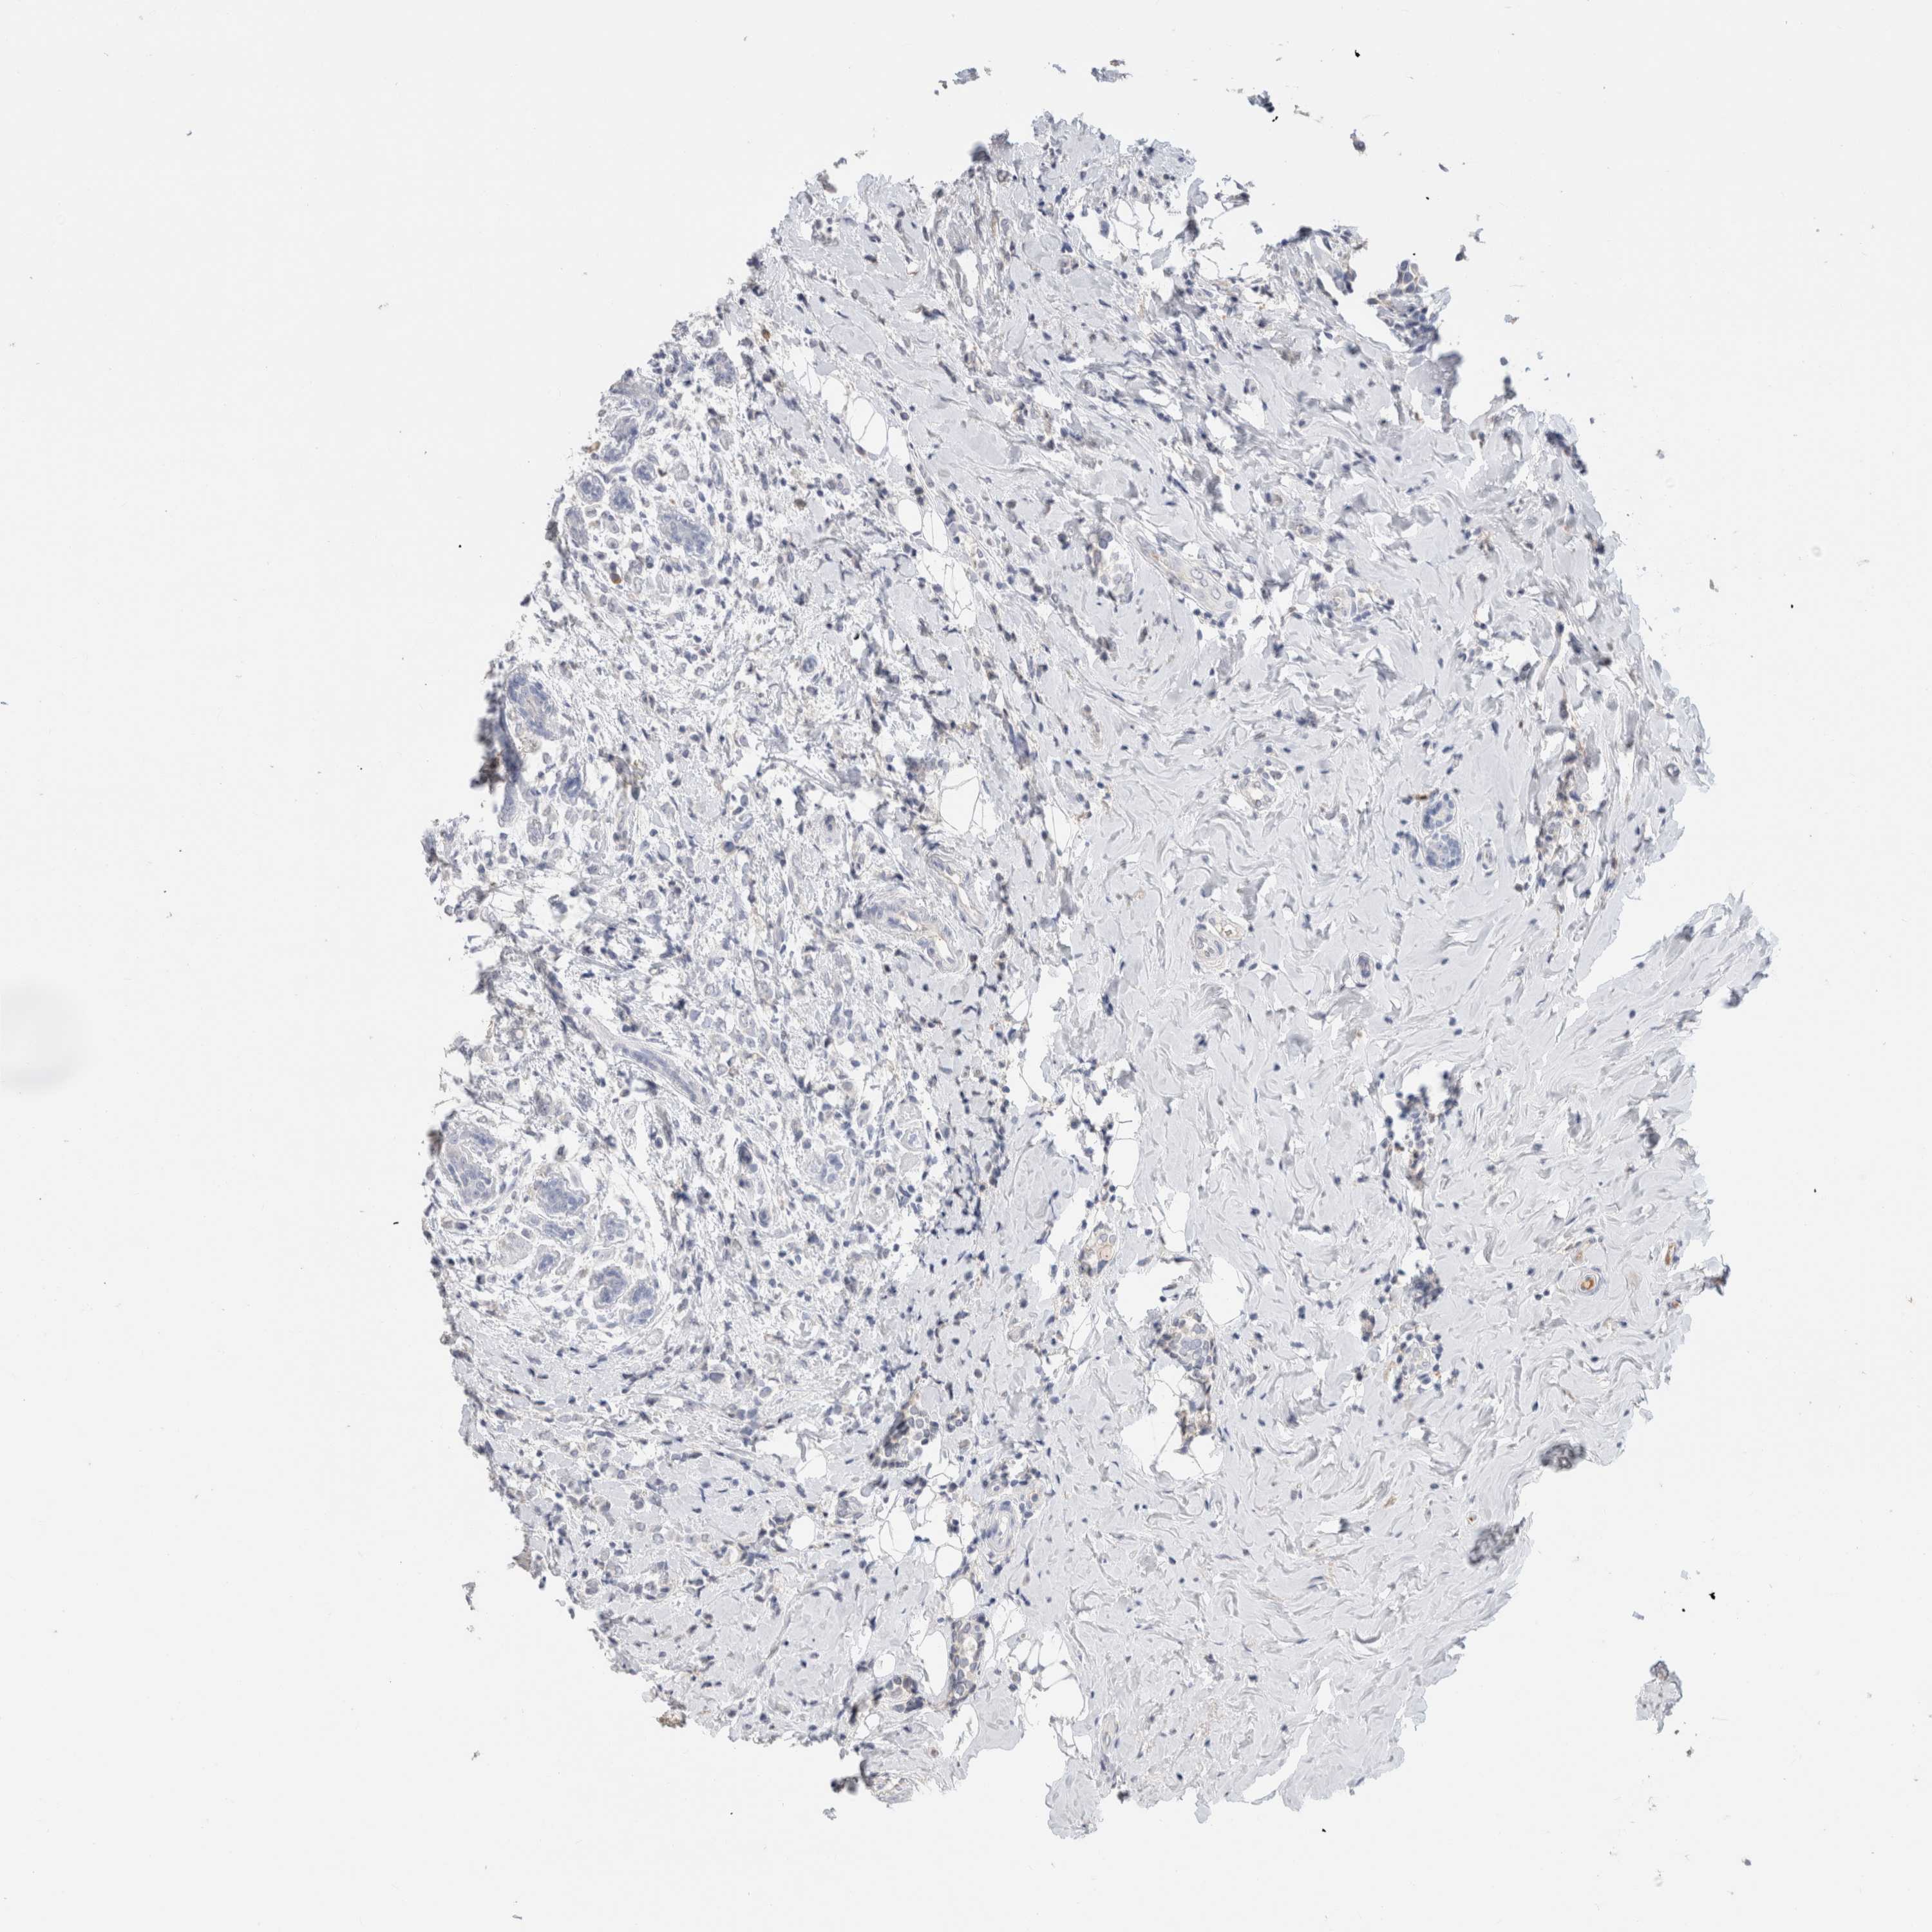

CANCER BREAST CANCER Show tissue menu

BRCA TCGA BRCA VALIDATION PROTEIN EXPRESSION